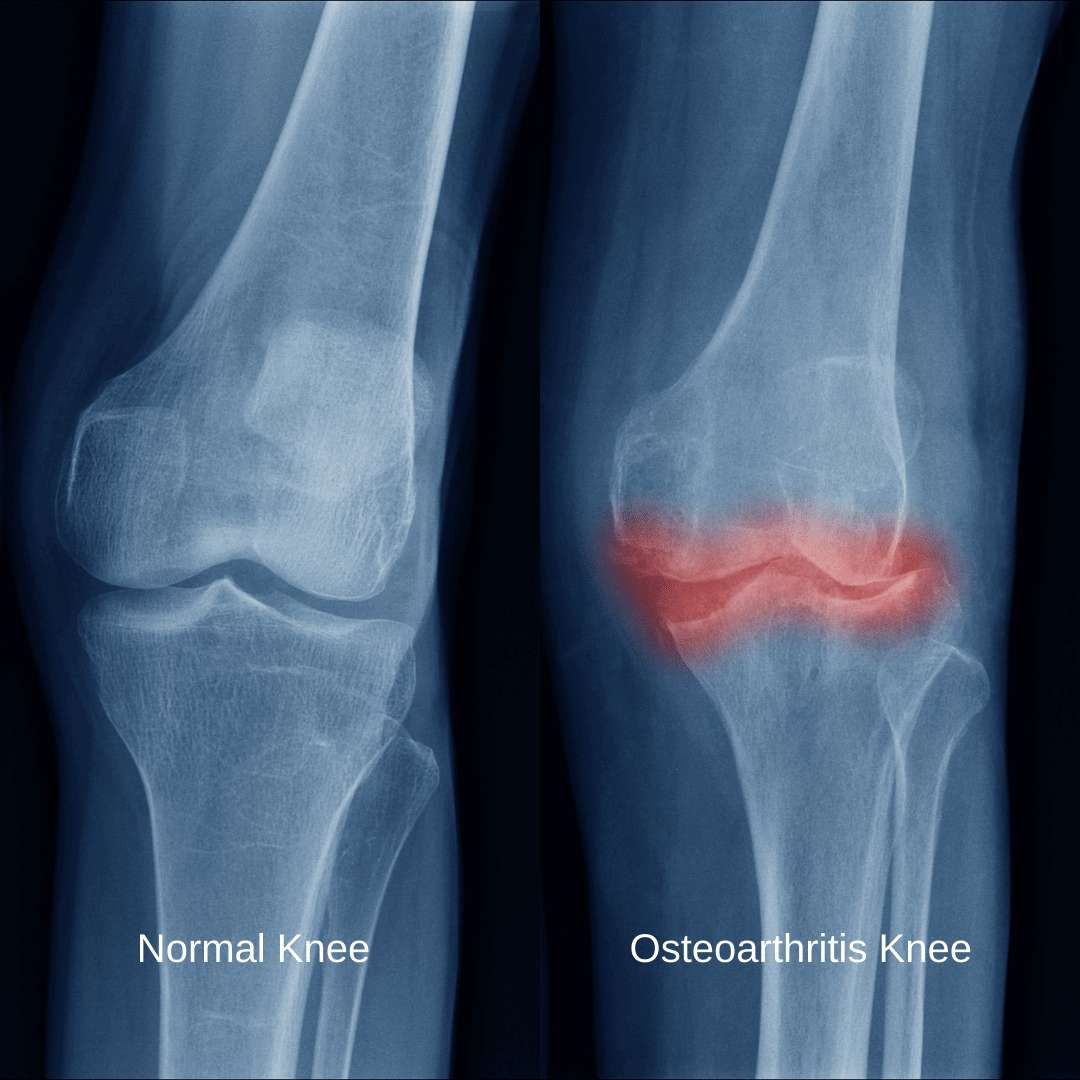

Two x-rays comparing a normal knee with an osteoarthritis kneeCartilage is the smooth tissue lining that cushions the ends of your bones and allows for smooth movement between the bones, resulting in frictionless joint movement. Unfortunately, your cartilage can gradually deteriorate and when it wears down enough from regular use, to leave the two bone ends to rub against one another, this creates pain and stiffness — this is what causes osteoarthritis.

Osteoarthritis is a degenerative joint disease that affects the cartilage, the protective tissue that covers the ends of bones in a joint. As the joints are repetitively used over time, the cartilage gradually breaks down, leading to pain, swelling, and reduced joint flexibility. As osteoarthritis progresses, the bones may develop bony growths (called osteophytes) at the joint edges, and the joint space may narrow, leading to stiffness and difficulty walking on the joints.

It was originally thought that osteoarthritis was only related to the gradual wearing down of this cartilage, however more recently, it has been observed that the entire joint and all of its components are involved. In addition to the cartilage thinning, osteoarthritis causes changes on the surface of the bone, deteriorates the connective tissues surrounding the joint, causes inflammation of the joint lining, and can lead to the development of bone spurs within the joints.